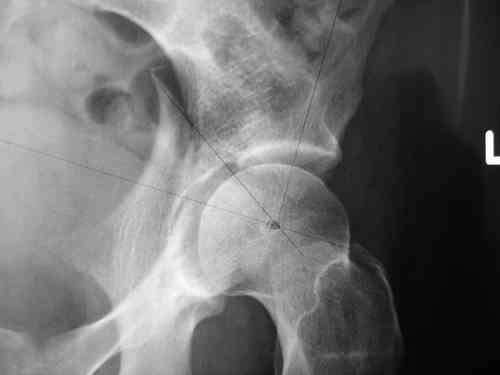

Дорогой Андрей. Мы имеем дело с комбинированной (ротационно и вертикально) нестабильностью таза со смещением правого гнемипелвиса. При таких переломах, фиксация только переднего полукольца вне зависимости от метода фиксации, как уже было сказано Djoldas Kuldjanov, M.D., не может создать адекватной фиксации. И перелом пластины был вполне ожидаемым после активизации пациента. Смещение сохраняется, и по-видимому не 2 см., а все 4, если не более. Разница всего (+2 см) по конечностям как вы указываете, скорее скомпенсировано позвоночником и протезом. Дополнительные снимки или КТ исследование помогли бы уточнить степень смещения с точностью до мм., выявить перелом поперечного отростка пятого поясничного позвонка, или помимо разрыва правого крестцово-подвздошного сочленения выявить перелом боковой массы крестца справа и т.д. При возможности, конечно, все это желательно сделать. Но мало что изменится с практической точки зрения, т.к. задача - это низведение репозиция и надежная фиксация правого гемипелвиса. Учитывая плачевный опыт стержневого аппарата, давность травмы совершенно очевидно, что поставленная задача достижима при открытой репозиции и одномоментной фиксации переднего полукольца с артродезированием правого крестцово-подвздошного сустава. Операция выполняется в положении больного на здоровом боку или полубоку из расширенного трансоссального подвздошно-пахового доступа с переходом на лонное сочленение доступом по Pfannenstiel. Указанный доступ обеспечивает подход к крестцово-подвздошному сочленению как спереди так и сзади. После артродезирования выполняется синтез лонного сочленения. Клинический пример

23.09.2003. Одновременный остеосинтез переднего и заднего тазовых полуколец

Результат через 10 дней

и 8месяцев после операции

> Результат через 10 дней и 8месяцев после операции

Да, забыл сказать - отличная работа, искренне восхищаюсь. Кость рубите по Judet (немного не разобрался по рисунку)?